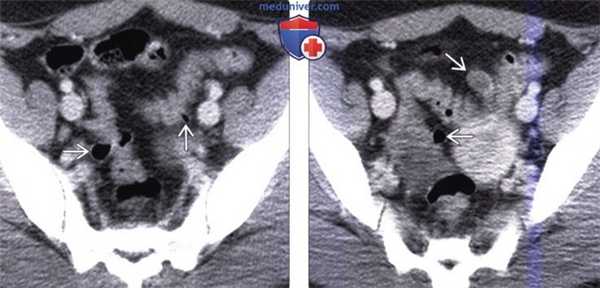

(Слева) На КТ у женщины 21 года, страдающей ожирением и сахарным диабетом, предъявляющей жалобы на чередование за -поров и диареи, визуализируются множественные дивертикулы, проецирующиеся вне поверхности сигмовидной ободочной кишки.

(Справа) На другом КТ срезе у этой же пациентки визуализируется еще один дивертикул. В настоящее время, наряду с эпидемией ожирения, дивертикулез обнаруживается даже у молодых людей, как в этом случае. И дивертикулез, и ожирение напрямую связаны с употреблением в пищу продуктов, богатых жиром и бедных растительными волокнами, а также с гиподинамией.

(Слева) На аксиальной КТ без контрастного усиления у мужчины 75 лет с ректальным кровотечением (гематокезией) визуализируется дивертикул правых отделов ободочной кишки.

(Справа) На КТ с контрастным усилением в артериальную фазу контрастирования у этого же пациента определяется активная экстравазация крови в просвет восходящей ободочной кишки, что является диагностическим признаком острого и тяжелого кровотечения, обусловленного дивертикулезом.

(Слева) На корональной КТ в этом же случае определяется накопление контрастированной крови в просвете ободочной кишки. Также визуализируется правосторонний дивертикул.

(Справа) Рентгенограмма (ангиограмма верхней брыжеечной артерии) позволяет подтвердить активное кровотечение из ветви правой ободочной артерии в просвет ободочной кишки. Дивертикулез - относительно частая причина ректального кровотечения.